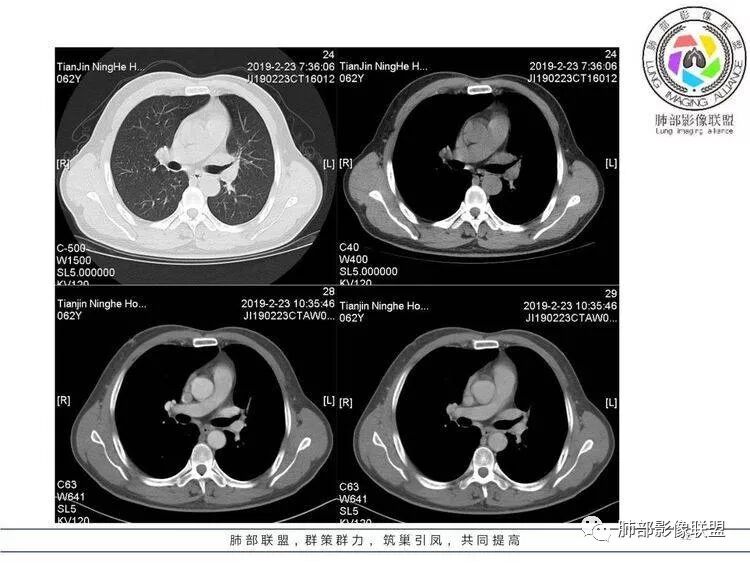

王秀仙:左肺上叶肿块,边缘平直收缩,周围可见长索条,轻度强化,密度不均可见低密度坏死,考虑结核。鉴别腺癌。Yiren  Sishui(厶水伊人):晨读:左肺上叶肿块,近胸膜侧光滑,提示符合淋巴回流病变,周围条索,符合肉芽肿性病变,环形强化,中心坏死,考虑结核可能luys:左肺上叶病变,沿支气管分布,边缘平直收缩,周围见长索条,轻度强化,伴边界可见低密度坏死灶。考虑特殊感染。灶内支气管中断,临床以咯血就诊,鉴别肿瘤。博麟:左上胸廓稍缩小,长条索病灶,冠状位似见支气管截断,坏死边界似乎欠清,猜个纤维条索基础上合并瘢痕癌红日东升:晨读:左上叶结块,前缘有粗大索条向前延伸,邻近前联合线明显左移,提示收缩明显。结块边缘平直、收缩;增强结块及索条明显强化,内血管走行自然,坏死灶周围似见三层结构;考虑炎性病变。wonderful:肿块实性边缘光滑  考虑良性病变 合并咯血 。结核或曲霉玫:左肺上叶不规则形软组织密度肿块影,边界清晰,期内密度不均匀,可见坏死,病灶向前呈条索状延伸,矢状位病灶形态欠规整,似有血管中断,考虑恶性病变可能,待除外结核?张帅:左肺上叶病变,病变周围平直,长毛刺,病灶内可见低密度区及支气管征,矢状位提示前段阻塞,病灶内气管不规则扩张,病灶周围有卫星灶,考虑良性病变:结核?我心飞翔:病灶边缘平直,中央可见坏死,周围磨玻璃边界欠清,考虑炎性病变张延军:左肺上叶尖后段肿块,边缘以平直为主,局部膨隆,内见片状坏死区,边界欠清,相应尖后段支气管闭塞,考虑占位并不张,腺癌?建议抗炎治疗后复查丽:左肺上叶病变,边缘平直,并可见长索条,增强后密度不均,可见坏死,首先考虑结核,但重建后支气管走形欠连续,似有截断,恶性待排毛勤香:左肺上叶病灶,边缘平直为主,周围索片影,增强强化不均匀,内有坏死,重建支气管走行欠规则,似有截断,老年男性,需排除恶性(鳞癌?)并阻塞性肺炎可能王萍:左肺上叶团片,大部分边缘平直、凹陷,周围见少许条片模糊影,增强内见坏死区,余区域较均质,其内支气管部分通畅,部分变窄。咯血病史,无发热,考虑肉芽肿性炎可能性大,结核或放线菌等,肿瘤待排THINKER:左上叶,占位,围绕尖后段支气管,U型凹丶平直,长索条,有轻强化及低密度,考虑良性的,首选OP,老年不发热丶咯血,鉴鳞癌、TB飞鹰行动:左肺病灶,有明显的收缩表现,增强后病灶内部可见低密度无强化区,病灶内支气管轻度扩张呈串珠状改变,支持炎性病变,结核可能性大。杨泽锋:支持炎性病变伴小脓腔形成,但不支持结核,因为病灶内可以可见血管影THINKER:问一下各位老师:这个给的强化,是肺动末期丶主动脉未期`延迟期?大雄:老年男性,左肺上叶前段条片状实变影伴周围长条索,境界清晰,边缘部分锐利光滑、部分毛糙,增强可见中央局部坏死,周围无强化区轻中度均匀强化,无钙化,无明显卫星灶,无胸膜明显牵拉凹陷。病灶整体收缩力有,张力不明显,肿瘤概率小。临床无明显急性感染症状,倾向于慢性增生性炎症,累及段支气管,引起了咯血。结核多见,但慢性结核肉芽肿一般强化没这么明显。OP不除外。老年男性如果有长期吸烟史,鳞癌不能完全排除,鳞癌的坏死强化都符合,鳞癌收缩力也不强,形态更是变化无常左手:老年男性,咯血,左肺上叶长条样结节,边缘见牵拉影,支气管堵塞,病灶内见坏死,坏死边缘偏清,考虑鳞癌,鉴别结核宇宙星空:支持恶性。鳞癌可能性大。支气管截断及空泡征

Shelia:考虑机化性肺炎伴小脓肿形成?炎性肌纤维母细胞瘤?鉴别癌食客:左肺上叶病灶,边缘平直,周围条片影,增强内见坏死区,内支气管部分通畅,咯血病史,无发热,考虑结核,肿瘤不除外。管洪林:左肺上叶尖后段病变,整体边缘平直,部分稍收缩,临近长索条影,胸膜缘可见轻度牵拉,增强后整体强化明显,其内可见低密度类圆形坏死区,边界清,首先考虑op并小脓肿形成,但部分层面显示小支气管受阻,是否层面原因?管洪林:若是支气管阻塞,鳞癌作为鉴别雪上一枝蒿(陈显静):他这个动脉期是不是不是很明显啊,觉得跟静脉期差不多,强化值也不好分辨?徐超:左肺上叶实变,边缘平直,周围无磨玻璃及卫星灶,病灶内坏死,强化后边界清楚,无壁结节,余病灶轻中度均匀强化(对比肌肉),增强后血管显影清楚自然,未见破坏边缘毛糙,血管旁条形无强化区(粘液?)整体符合炎性特点,炎性假瘤或op可能,伴小脓肿;结核放后面待排(结核病灶内血管完好,边缘清楚,且强化近中度,不是很合理,肉芽肿到也可以)。红日东升:平扫和强化窗宽窗位不一样良孑:左上实变,有平直及长毛刺,其内支气管牵拉性扩张,提示收缩力较强,无卫星灶,强化不支持TB,均匀强化,无分叶不支持鳞癌,影像上提示慢性进程,考虑OP并脓肿,鉴别炎肌母。